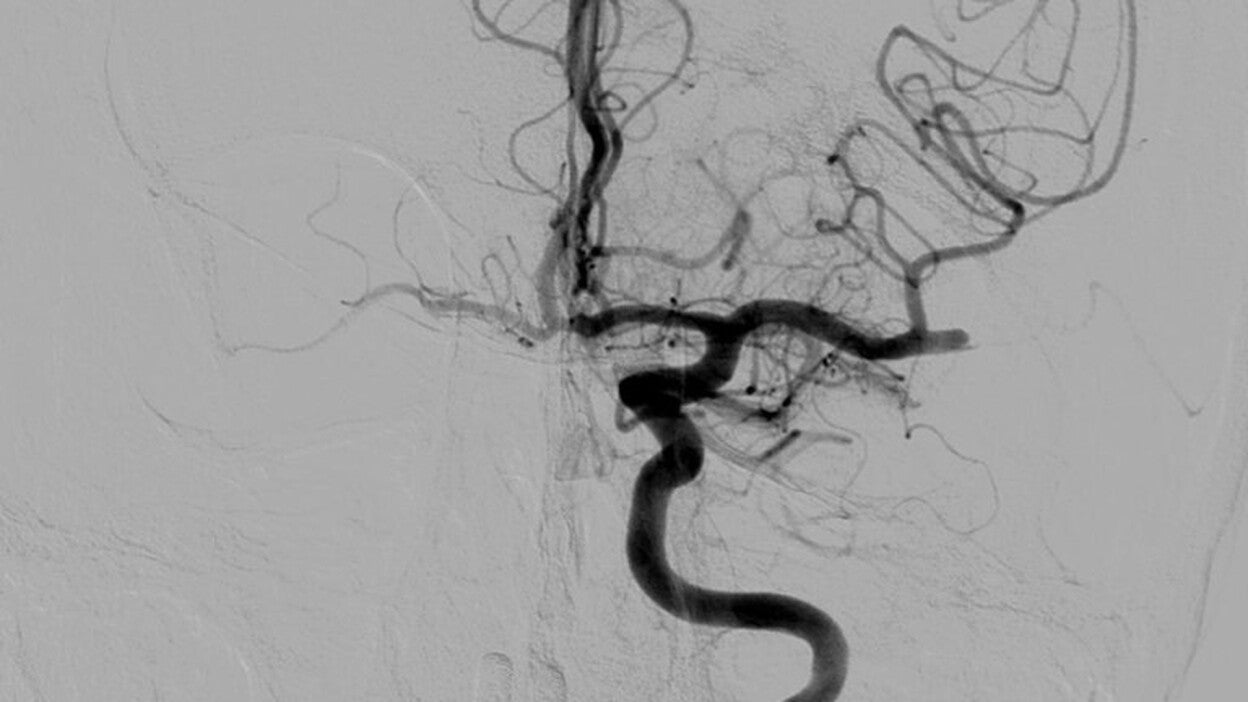

El procedimiento, realizado en la sala de radiología vascular intervencionista se pone en marcha una vez diagnosticada la obstrucción de la arteria intracerebral mediante TAC. Ya en sala se realiza una arteriografía para confirmar los hallazgos y valorar la posibilidad de extraer el trombo o coágulo en el paciente candidato.

Para ello se introduce un catéter a través de la arteria femoral hasta la arteria carótida interna del lado afecto, para posteriormente, y a través de este mismo catéter, introducir otro más fino denominado microcatéter que será el responsable de acceder a la arteria intracerebral que presenta el trombo. Una vez en la zona se coloca un dispositivo que actúa en forma de red (stent-retriever) que permite 'atrapar' y recuperar el coágulo de sangre, para finalizar retirando el stent del mismo modo que se efectúa con los catéteres y así comprobar que la arteria vuelve a ser permeable.